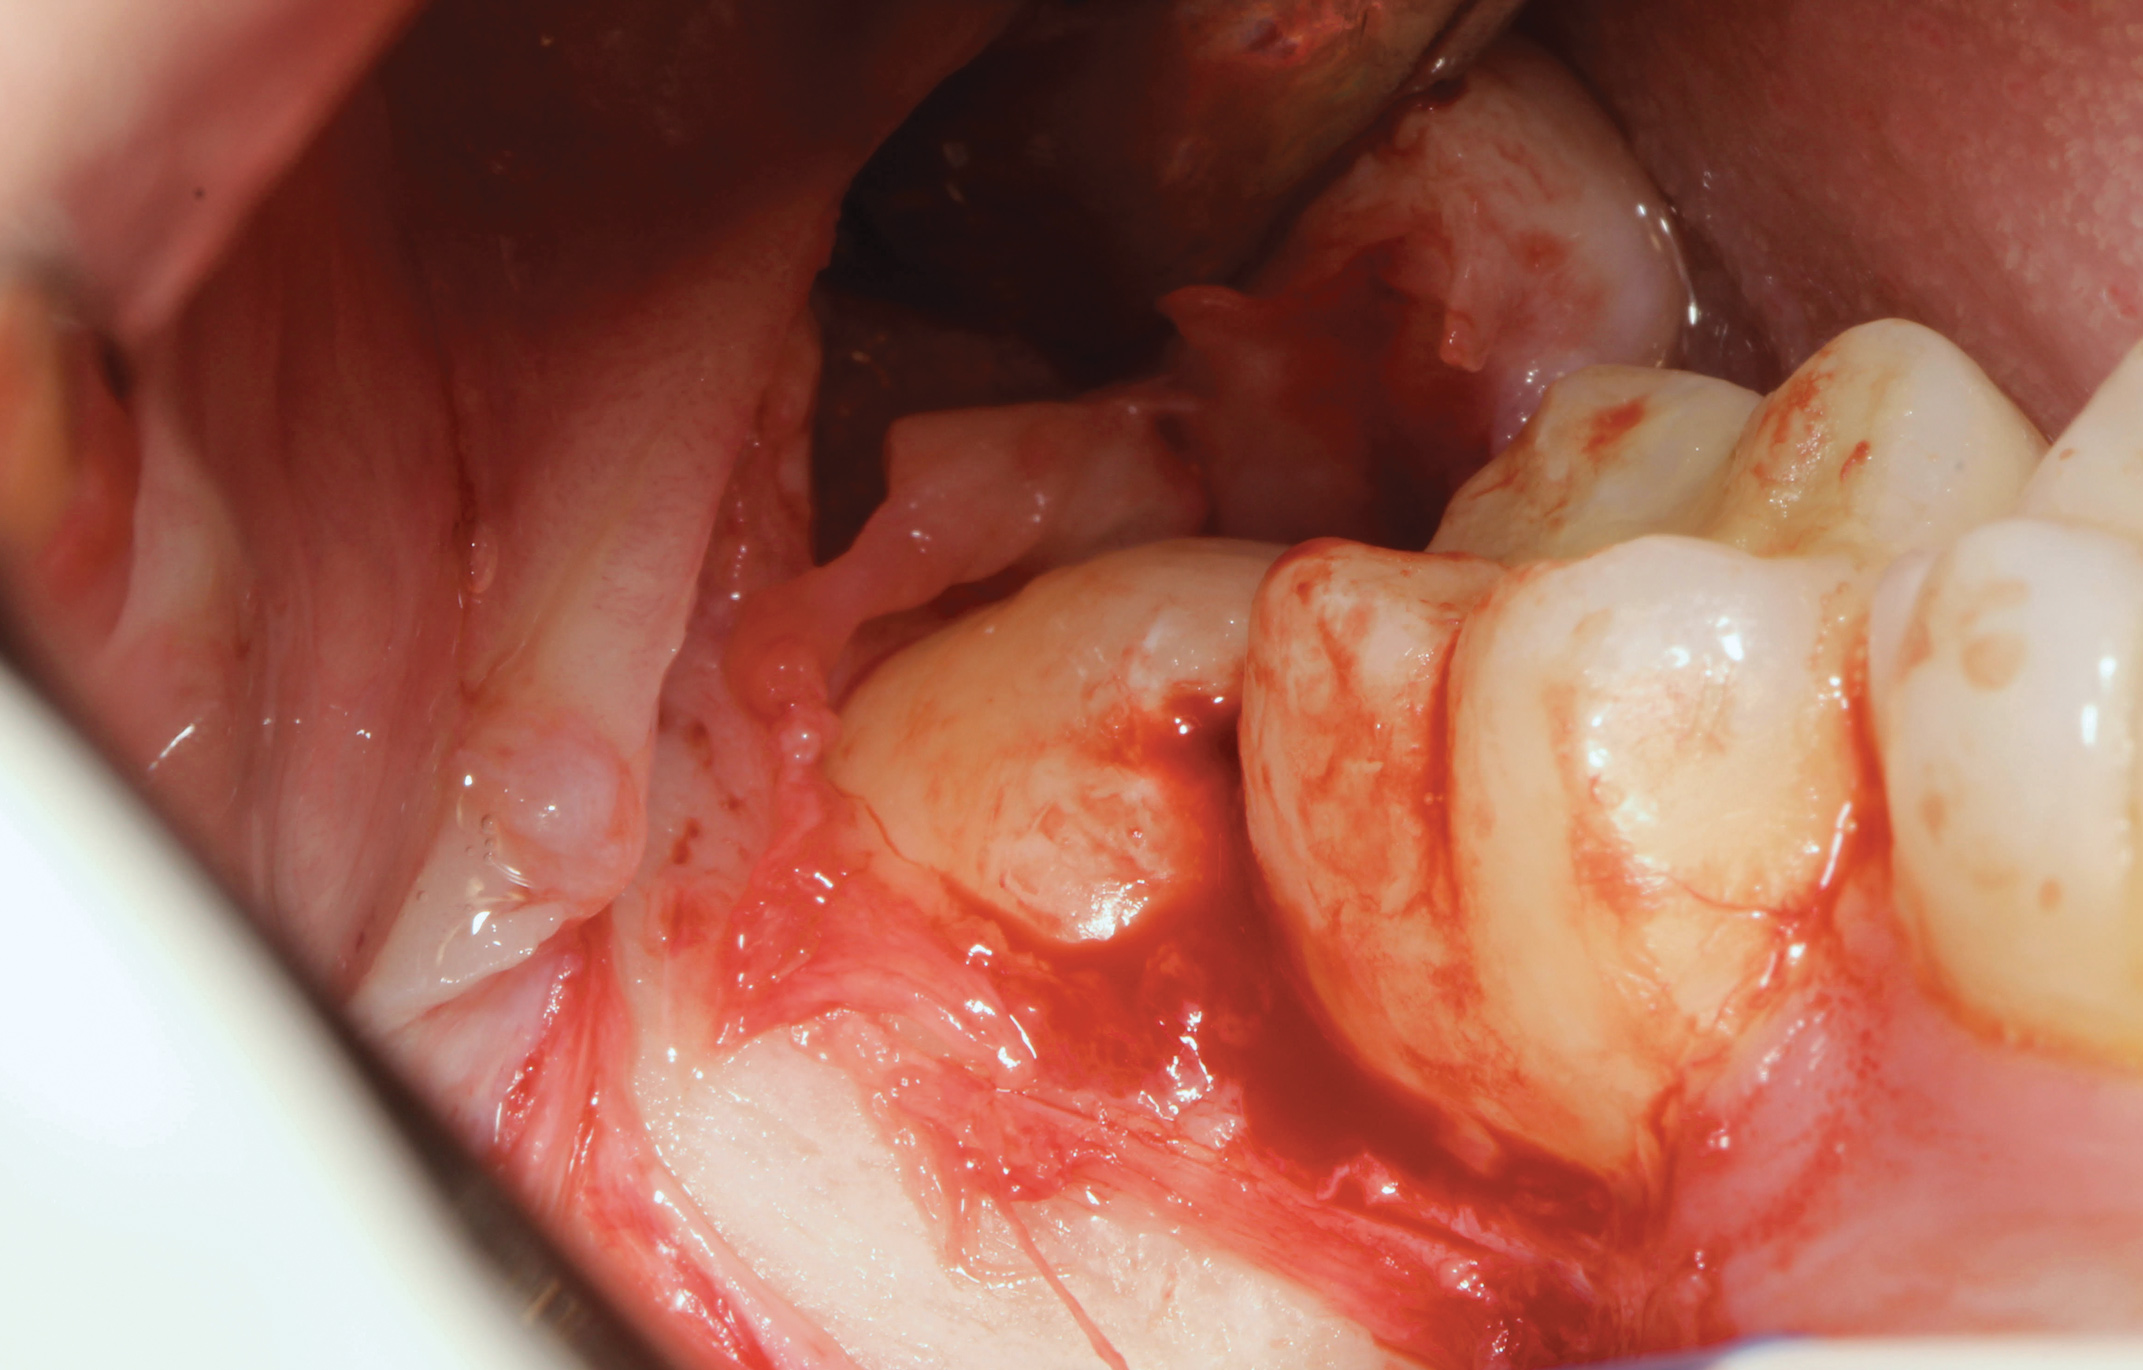

The extracted tooth fragments were cleaned to remove caries if present as well as periodontal ligament (PDL) remnants (Figure 4). The tooth was ground into particles using the dentin grinder machine. The particles were then saturated for 10 minutes in a dentin cleanser solution (sodium hydroxide solution mixed in 20% ethanol); this was followed by a phosphate buffered saline wash, resulting in a bacteria-free, autogenous graft material ready for implantation (Figure 5).

The ADG was packed into the osseous defect related to the extracted tooth and allowed to moisten with the patient's blood in the site. Sterilized gauze was used to remove any residual wetness from the site, resulting in a well-packed socket with ADG (Figure 6). The ADG was then overlaid with an absorbable hemostatic gelatin sponge, and the flap was closed by primary intent with 4-0 vicryl sutures (Figure 7). For the control group the same surgical protocol was employed except for the use of the ADG; the hemostatic sponge was placed prior to site closure. A blood clot was formed using a surgical curette and the flap was closed with 4-0 vicryl sutures.

Fig 4. Soft tissue (PDL), decay, and any residual restorative material was removed prior to the tooth being processed in the dentin grinder for creation of the graft material to be placed into the extraction socket.

Figure 4

Fig 5. Autogenous dentin graft material after the extracted tooth was processed using the dentin grinder system. The material was now ready for placement into the extraction socket.

Figure 5

Fig 6. Extraction socket filled with the autogenous processed dentin prior to flap closure.

Figure 6